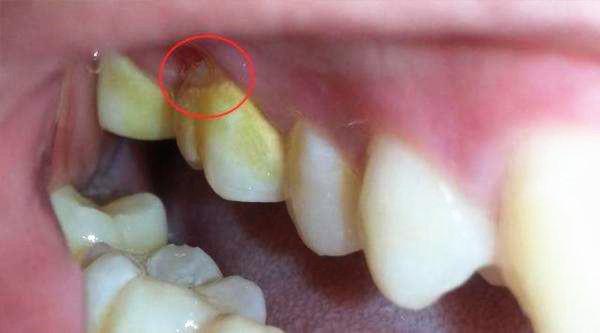

看起来呈黄白色的软软的物质其实就是未清理干净的留在牙齿表面的食物残渣。

微小肉眼不可见的物质在长期积累下,形成了肉眼可见的泥垢,而这种泥垢正是牙结石的前期形态,再经过更长时间的积累和钙化就会形成难以去除的牙结石。

3,牙结石。这种黄白色的泥垢如果不能够及时清理掉的话,是会和人体的唾液以及牙菌斑发生一些化学反应从而形成牙结石。一旦形成牙结石,刷牙是不能够解决问题的,就需要患者去医院进行洗牙来处理。